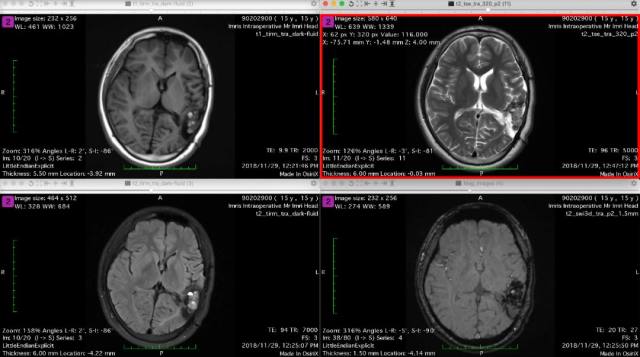

2、术前影像资料

图 2 术前 MRI:左颞顶枕血管畸形术后;混杂信号;考虑畸形残余伴出血。